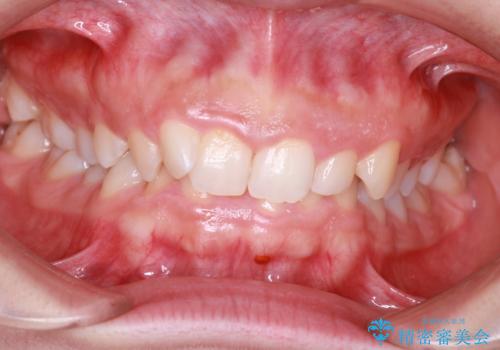

- 前歯の凸凹と顎の偏位を主訴に来院されました。

下顎の偏位を認めましたが、外科矯正を希望されなかったためできる範囲で顎の偏位を治すことができるよう治療を行なっております。